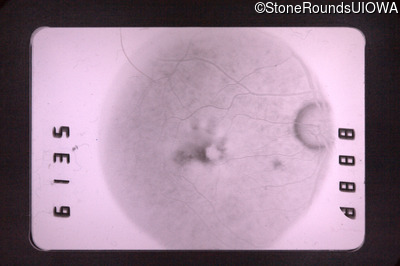

Fluorescein Angiography - Left - 20/40 +3

Exemplar